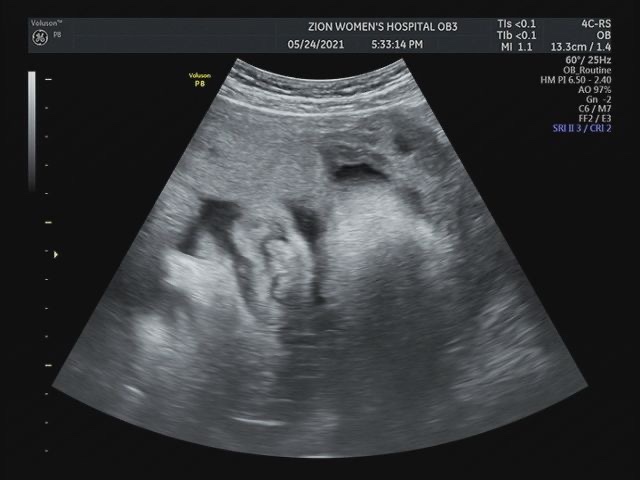

(38주~39주) 정기검진, 태아몸무게, 태동검사, 내진

38주 정기검진 37주부터는 1주일에 한번씩 병원을 오라고해서 6/12에 병원을 갔다 태동검사했는데 아직 잘 ...

(33주~37주) 막달검사, 태아 몸무게, 정기검진

33주이후 증상 1. 태동이 눈이 보임 배가 급격하게 나오고 태동이 눈에 보이기 시작했다 동영상 찍는건 항...